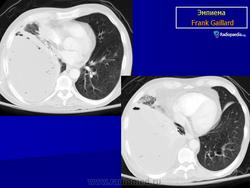

Гнойный ТП (эмпиема). Туберкулез плевры, сопровождающийся накоплением гнойного экссудата, представляет собой особую форму экссудативного плеврита – эмпиему. Развивается при распространенном казеозном некрозе плевры. Гнойный ТП может начинаться в связи с прорывом каверны в плевральную полость и образованием бронхоплеврального свища. В этом случае заболевание проявляется клиническими симптомами спонтанного пневмоторакса с явлениями острой дыхательной недостаточности. Лишь через несколько дней у таких больных развивается симптоматика гнойного плеврита, осложненного бронхоплевральным свищом.

При рентгенологическом исследовании в проекции пристеночной части плевральной полости выявляется полостное образование, заполненное гноем и казеозными массами. При пункции плевральной полости и попадании воздуха возможен горизонтальный уровень жидкости.

При ультразвуковом исследовании плевральной полости определяется полость различных размеров и глубины, заполненная в основном фибрином.

Эмпиема плевры.

Гнойным плевритом или эмпиемой плевры называют скопление гнойного выпота в плевральной полости.

Если гнойный плеврит сопровождается значительной деструкцией легкого, то внутренней границей осумкованной полости эмпиемы может являться не висцеральная плевра, а разрушенная и деформированная паренхима легкого. Подобная картина может возникать и в тех случаях, когда гнойному расплавлению подвергается наружная стенка обширного солитарного субплеврально расположенного абсцесса легкого. Характерным рентгенологическим признаком такой "абсцесс-эмпиемы" является неровная, изъеденная и утолщенная медиальная стенка полости. Наиболее точно определить наличие жидкости в полости плевры и локализовать внутриплевральное осумкование позволяет компьютерная томография. Значительную пользу для правильной диагностики осумкованных полостей и бронхоплевральных свищей может принести введение контрастного вещества в полость - плеврофистулография.